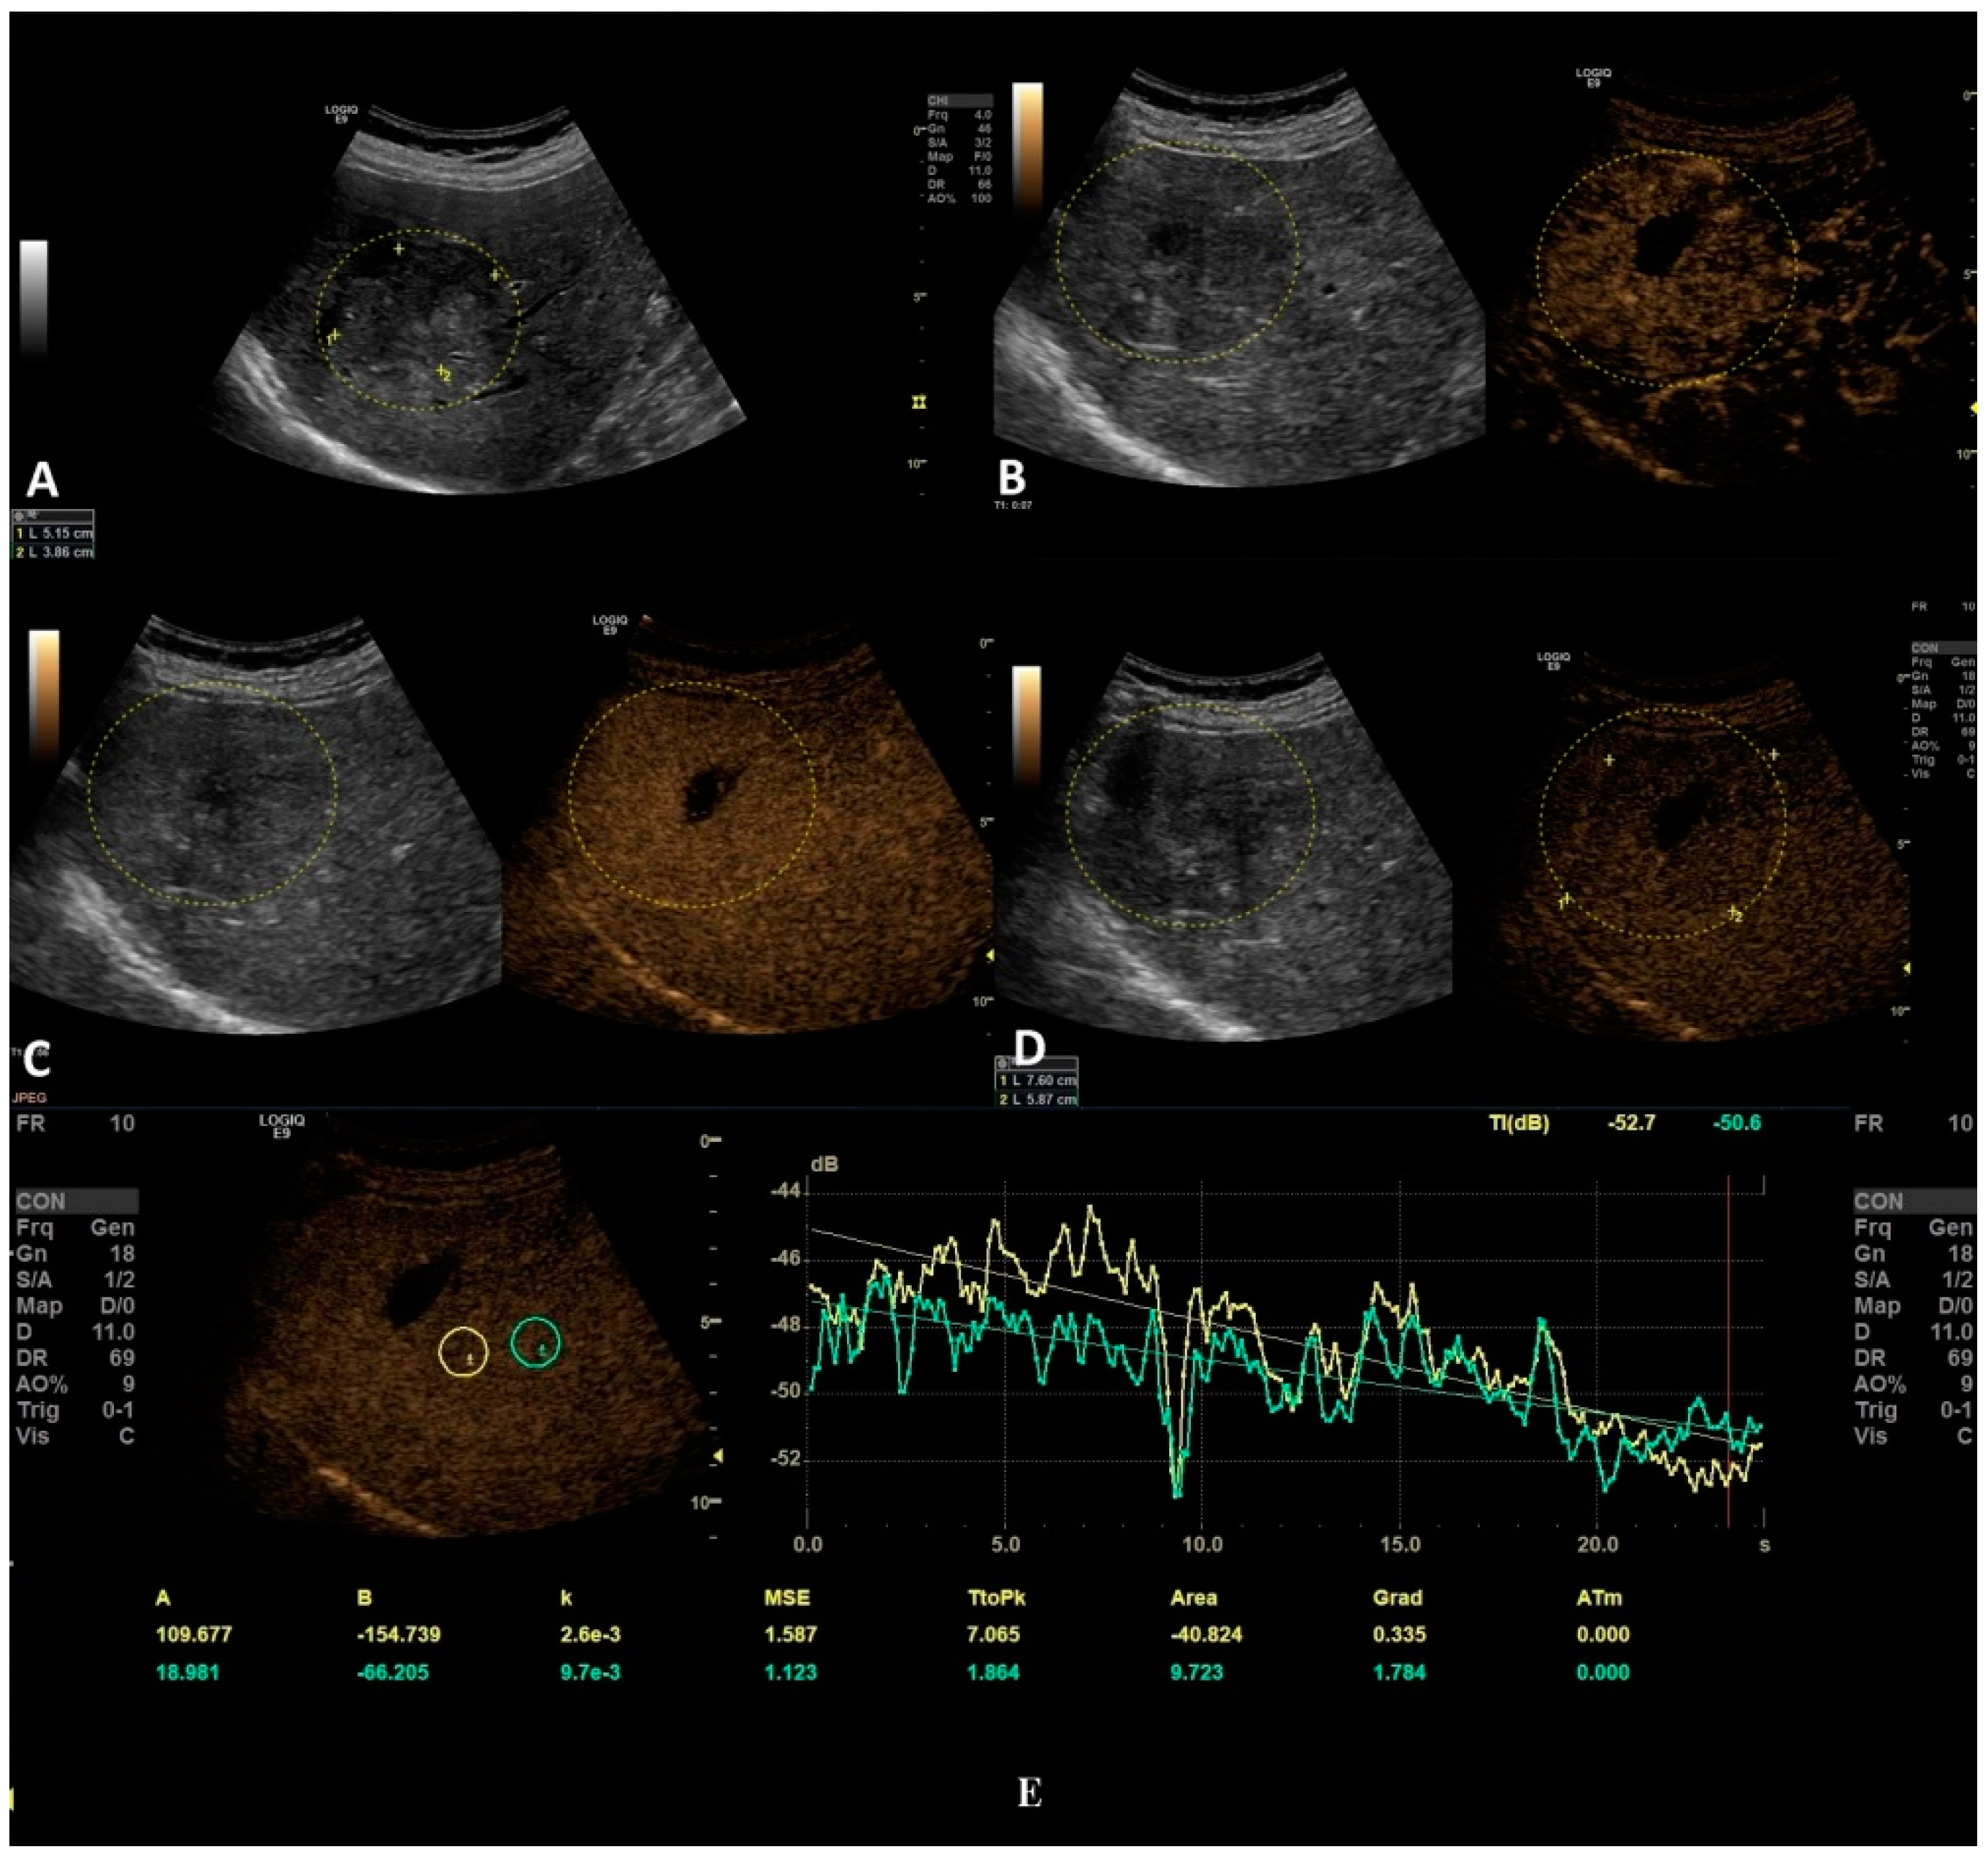

Figure 5. In this setting, a malignant lesion was assessed, as depicted in B-mode (A). CEUS evaluation is depicted in frames (BD). In frame (D), the enhancement pattern is not recognizable; thus, TIC analysis (E) was applied. The results revealed objective washout phenomena (the graphs are intersecting one another).